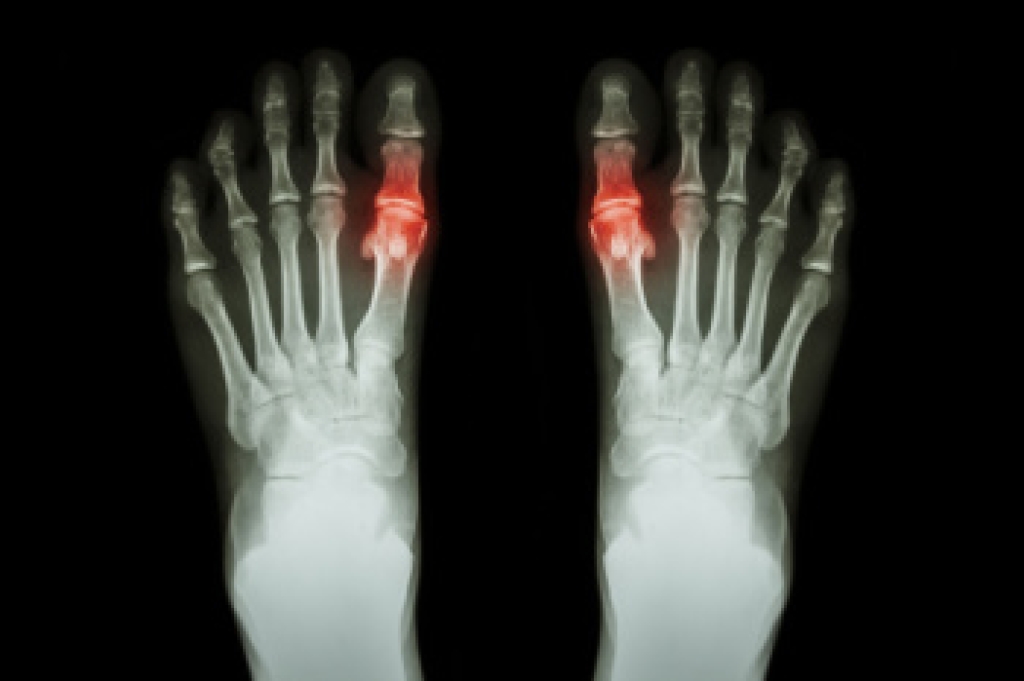

To figure out the cause of foot pain, podiatrists utilize several different methods. This can range from simple visual inspections and sensation tests to X-rays and MRI scans. Prior medical history, family medical history, and any recent physical traumatic events will all be taken into consideration for a proper diagnosis.

- Arthritis (such as Gout, Rheumatoid, and Osteoarthritis)